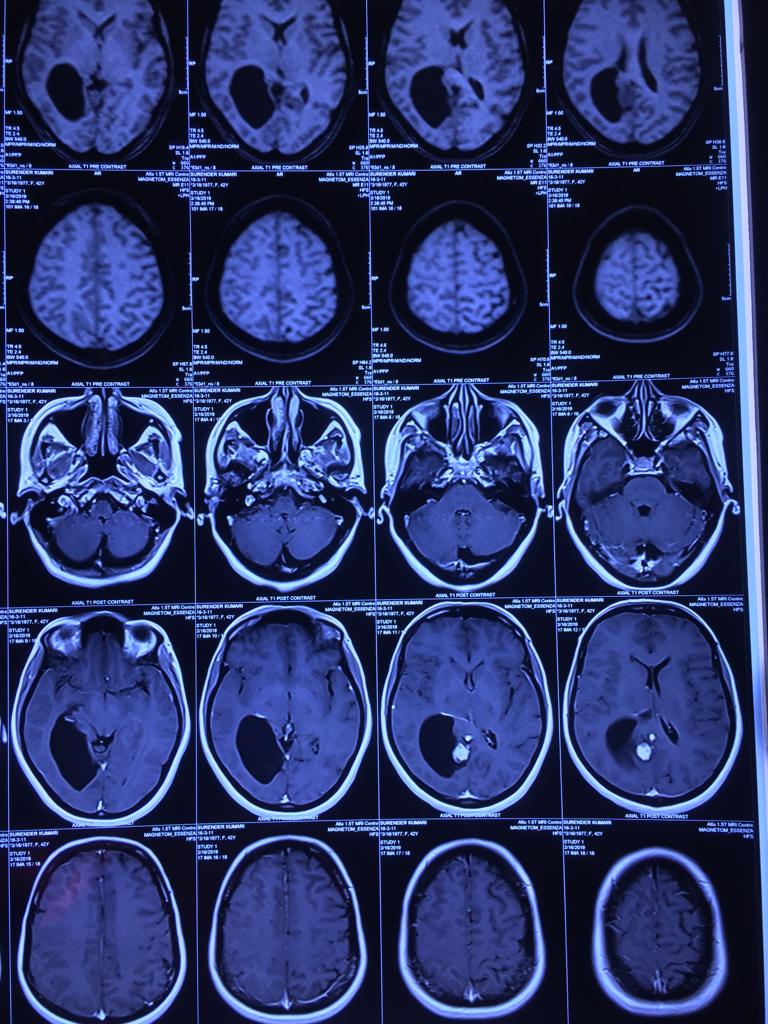

Cases